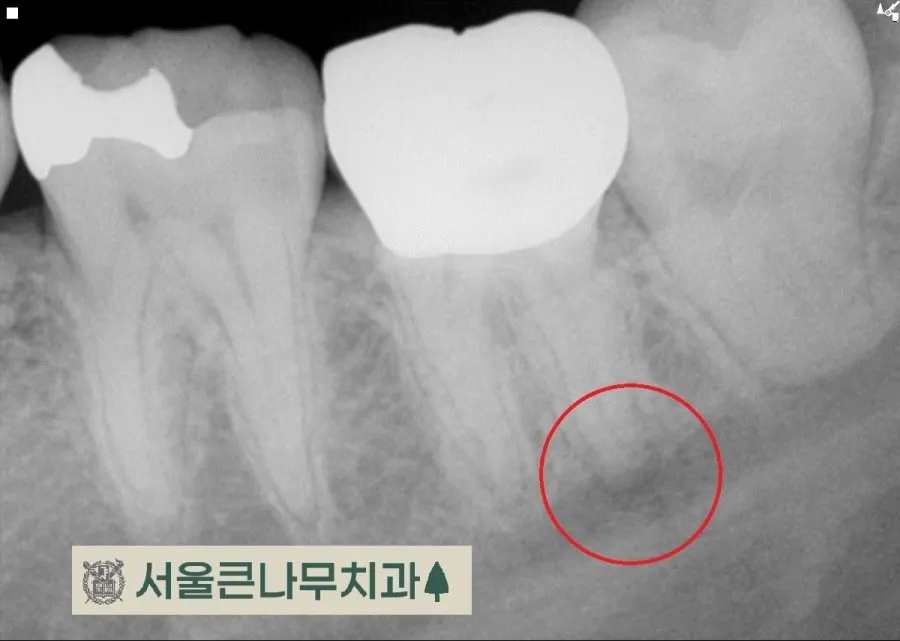

통증이 있는 치아에는 기존에 때웠던 레진 수복물이 있었고 겉보기에는 문제가 없어 보였지만,

자세한 진단을 위해 CBCT 촬영을 해본 결과, 동그라미 친 부위에 뿌리끝 염증이 발견되었습니다.

이전에 치료했던 레진 수복물이 치수에 가까워 신경에 영향을 주었을 것이라고 판단하고 신경치료에 들어갔습니다.